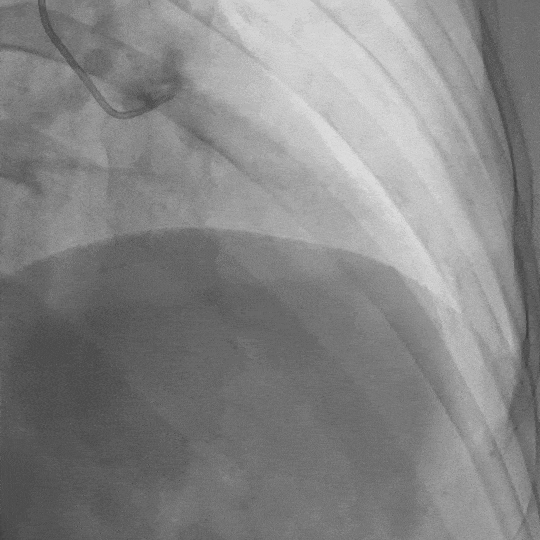

影像素材 | 患者冠状动脉造影1:前降支中段长段心肌桥,收缩期管腔重度狭窄

影像素材 | 患者冠状动脉造影2:前降支中段长段心肌桥,收缩期管腔重度狭窄

“我们发现,问题主要出在那个心肌桥上。”李医生指着影像解释道,“CT上看到的心肌桥,在造影下原形毕露。在心脏收缩时,这段覆盖在血管上的心肌会像承受“紧箍咒”一样,用力挤压下面的血管,压迫程度最高时甚至达到了90%!”

这就能解释为什么常规检查会“失灵”了。心电图捕捉的是静态或负荷状态下的心电信号,普通CT也难以观察到动态的血管压迫。而李延林医生通过层层递进的精准检查,终于找到了那个在“动态”下才暴露出来的“元凶”——因严重心肌桥压迫导致的心肌缺血,进而诱发了晕厥。